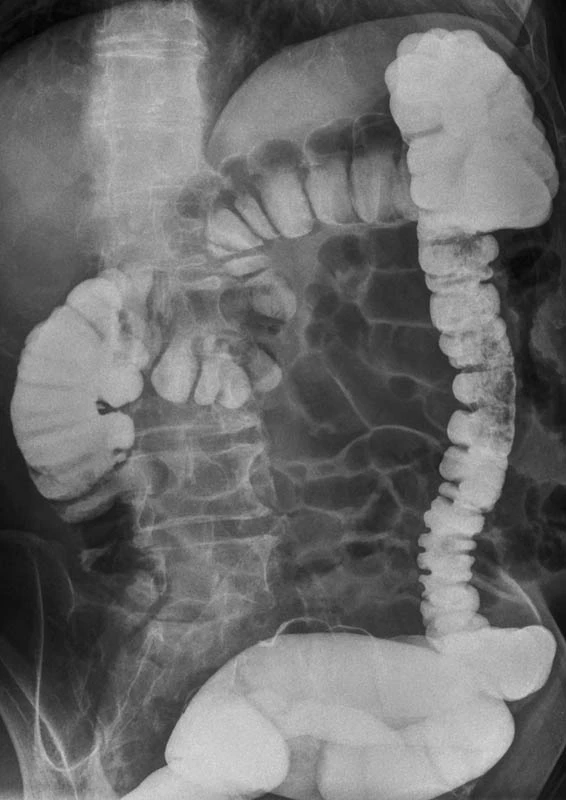

Контрастную рентгенографию верхних отделов ЖКТ врачи назначают пациентам довольно часто при таких заболеваниях, как язва, гастрит, грыжа желудка, новообразования в виде опухоли и др. Сульфат бария при этом используют для контраста: он отражает рентгеновские лучи и позволяет получать более детальные снимки. Обычно пациенты принимают препарат внутрь перед исследованием и во время него.

— Для этих целей можно применять только медицинский порошок для приготовления суспензии «Бар-Випс». Он является единственным зарегистрированным лекарственным препаратом сульфата бария в России, — прокомментировал врач-рентгенолог Елизаветинской больницы Дмитрий Демченко. — При контролируемом использовании медицинского бария в момент обследования получить отравление практически невозможно. «Бар-Випс» является гипоаллергенным контрастным препаратом, не всасывается в желудочно-кишечном тракте и выводится естественным путем. Это максимально снижает шансы вызвать побочную реакцию.

— При проведении рентгеновского исследования необходимо использовать исключительно лекарственный бария сульфат, поскольку он является водонерастворимым, — объясняет руководитель отдела клинической токсикологии НИИ скорой помощи им. Джанелидзе, главный внештатный специалист-токсиколог МЗ РФ в СЗФО, д. м. н. Алексей Лодягин. — Барий — токсичное вещество. Если принять немедицинский водорастворимый барий, который вместе с водой всасывается в кровь и попадает в организм, то он вызовет острое отравление, очень серьезное, которое может повлечь ожог пищевода, тошноту, рвоту, диарею, нарушение ритма сердца, нарушение нервной и любой другой проводимости, нарушение чувствительных и двигательных функций вплоть до развития параличей.